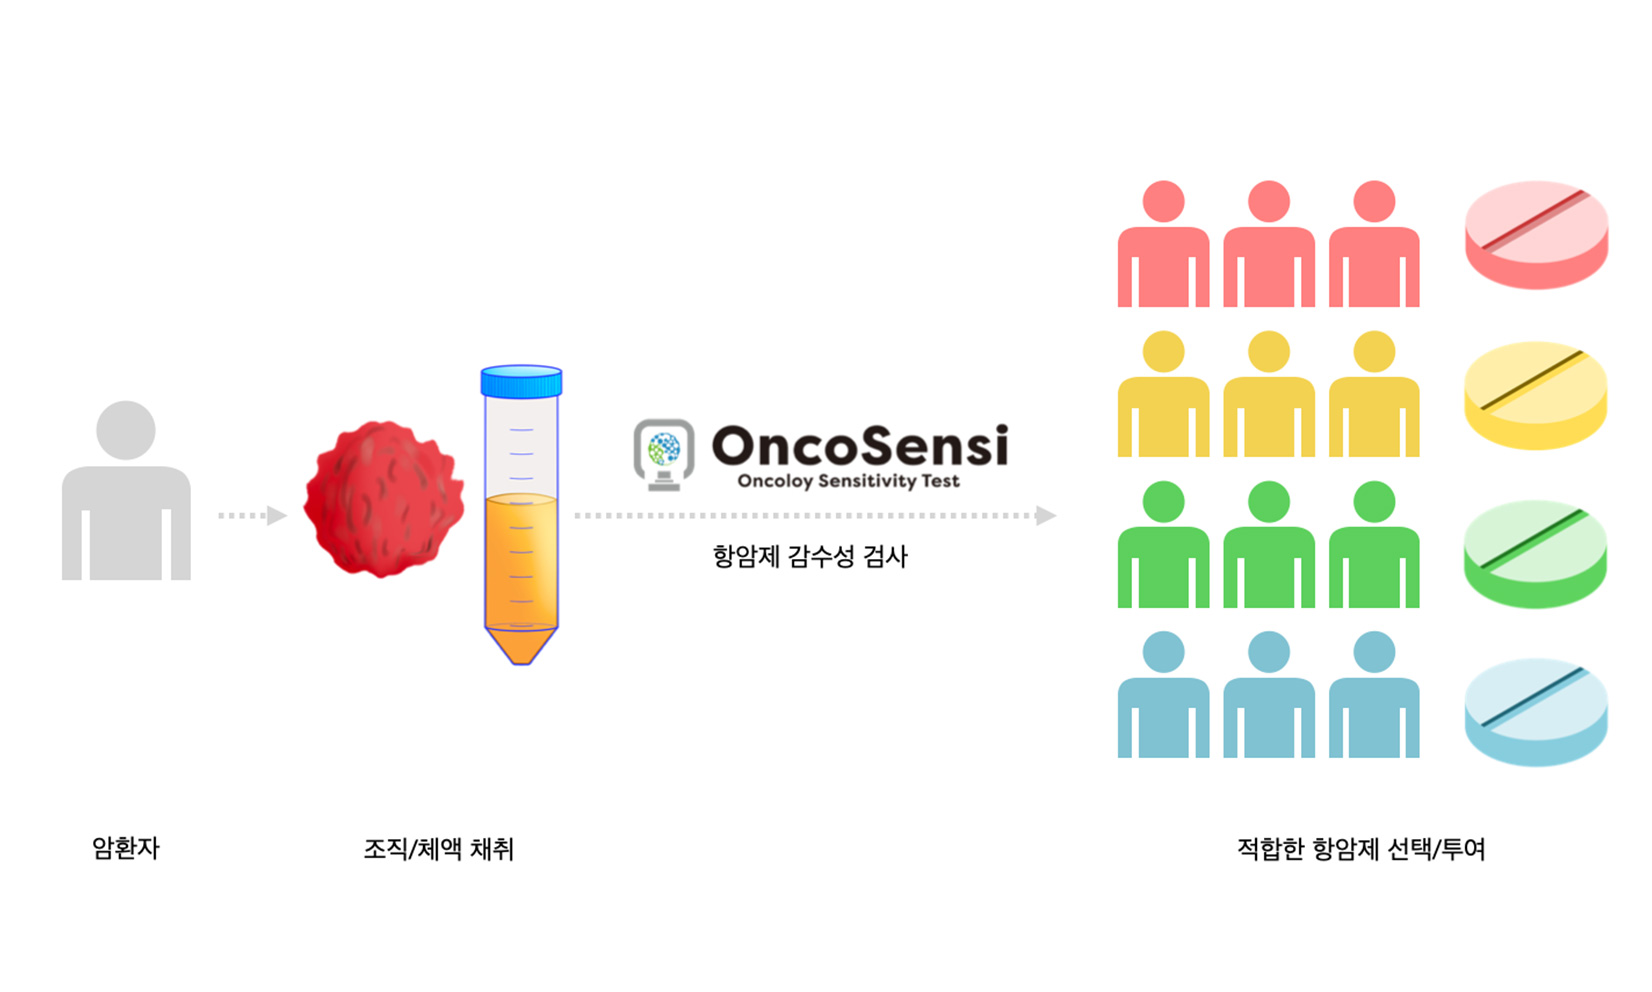

Precision medicine for your cancer

효과가 다른 항암제,나의 암세포에서 답을 찾다.

온코센시와 함께 나에게 맞는 항암치료를 시작하세요.

개인 맞춤형 항암제 감수성 검사 서비스

다양한 암세포의 항암제 반응 결과와 암환자들의 실제 치료 정보들을 연계한 빅데이터를 기반으로 분석하여 신뢰도 높은 타겟 항암제 제안합니다.